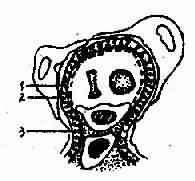

7.新月体性肾小球肾炎或毛细血管外性肾小球肾炎病变肾小球毛细血管壁严重变性坏死,血细胞及大分子纤维蛋白大量漏出,刺激肾小球囊壁层上皮细胞明显增生,因而形成上皮性新月体,进而纤维化形成纤维性新月体,新月体体积增大,将肾小球囊腔填塞,变性坏死的毛细血管袢被挤压于血管极的一侧(图4-2-8)。上述病变的肾小球必须占全部肾小球50%以上,才称为新月体肾炎,这是与其它类型肾小球疾病伴有少数新月体形成的鉴别点。电镜下可见肾小球基膜严重变性或断裂,并可在基膜不同部位发现电子致密物。荧光检查可见IgG和C3沿毛细血管壁沉积,部分呈线状排列,部分呈颗粒状排列,临床表现呈急进型肾炎。

图4-2-8 新月体性肾小球肾炎模式图 壁层上皮细胞增生形成新月体,肾小囊封闭,毛细血管袢受挤压(左侧为正常肾小球模式图)

1.肾小囊壁层 2.上皮细胞 3.内皮细胞 4.系膜细胞及基质 5.新月体